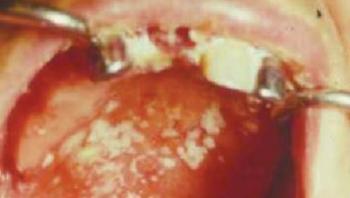

A ritkábban előforduló nem homogén csoportba tartozik a verrucosus típus, melyet exophyticus hámmegvastagodás, valamint szabálytalan kiemelkedések jellemeznek (10.6. ábra10.8. ábra). A noduláris leukoplakia a nyálkahártyából kiemelkedő, kerek, piros vagy fehér kiemelkedésekkel tarkított elváltozás, melyet gyakran a homogén vagy verrucosus leukoplakia Candida albicanssal történő felülfertőződése okoz. Az erythroleukoplakia fehér lézió, melyet vörös, erosiós területek szakítanak meg. Valamennyi típus közül leginkább ez utóbbinál számíthatunk arra, hogy a betegnek panaszt okoz, de természetesen ez is lehet teljesen panaszmentes. Ennél a típusnális gyakori a candidiasis jelenléte, ami egyrészt növeli a malignizáció veszélyét, másrészt módosítja a terápiás tervet.

10.6. ábra. Verrucosus leukoplakia a szájfenéken